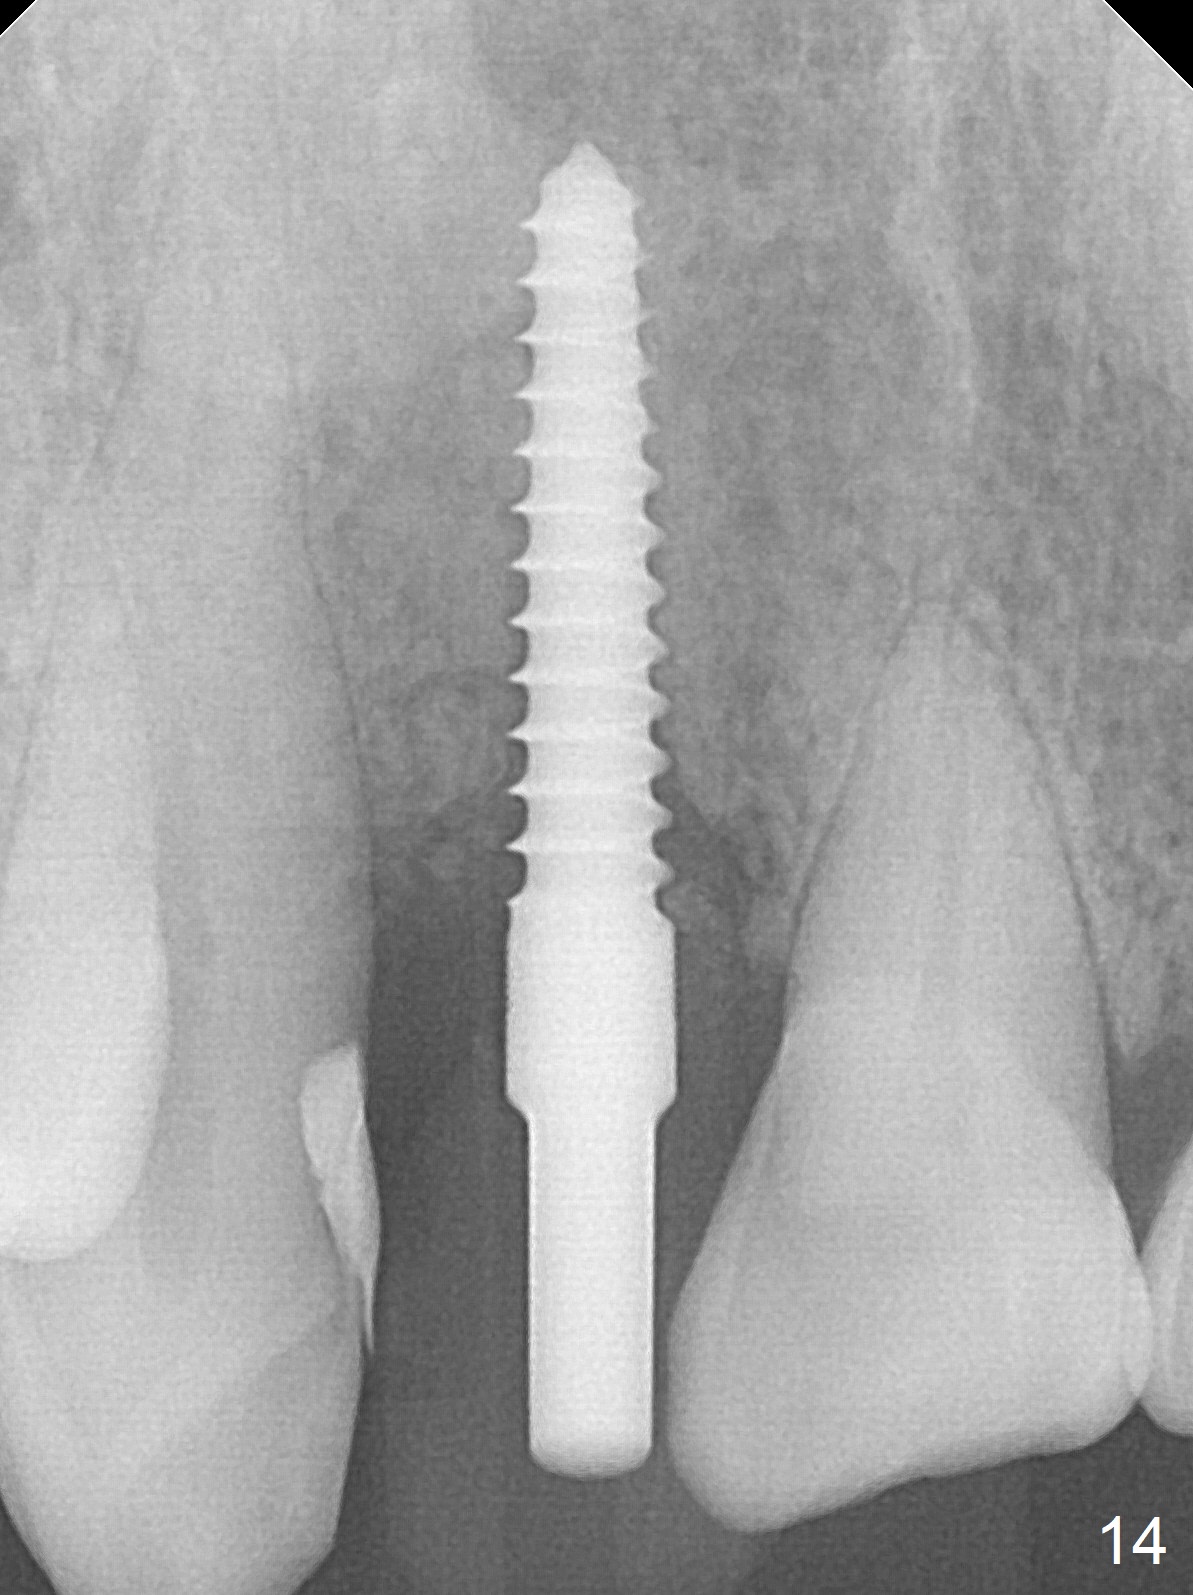

Sixteen days postop, the patient is doing fine, although the labial fistula has not disappeared (Fig.8 <). The detached distolabial papilla is healing (Fig.9 *) with mild bone graft exposure (^). The lacerated distopalatal papilla is also healing (Fig.10 *). These complications are related to flap surgery. The apical portion of the socket appears to have reduced 4 months postop (Fig.14). When the definitive restoration is delivered 5 months postop, there is gingival recession, including the distal of #8 (Fig.11 arrows, which is expected to improve over time) due to flap surgery. The labial plate collapse is minimal (Fig.12 *), while the palatal laceration (Fig.10) has healed (Fig.13). When the patient returns 1.5 years post cementation, there is increased bone density next to the coronal portion of the implant, equivalent to the bone graft (Fig.15 *). The fistula is absent (Fig.16). The crestal bone loss remains 2.5 years post cementation (Fig.17 *), although there is no sign of periimplantitis (magnification). Oral hygiene is poor. There is no change in the soft (gingival recession; data not shown) or hard tissues 3 years 8 months post cementation (Fig.18).